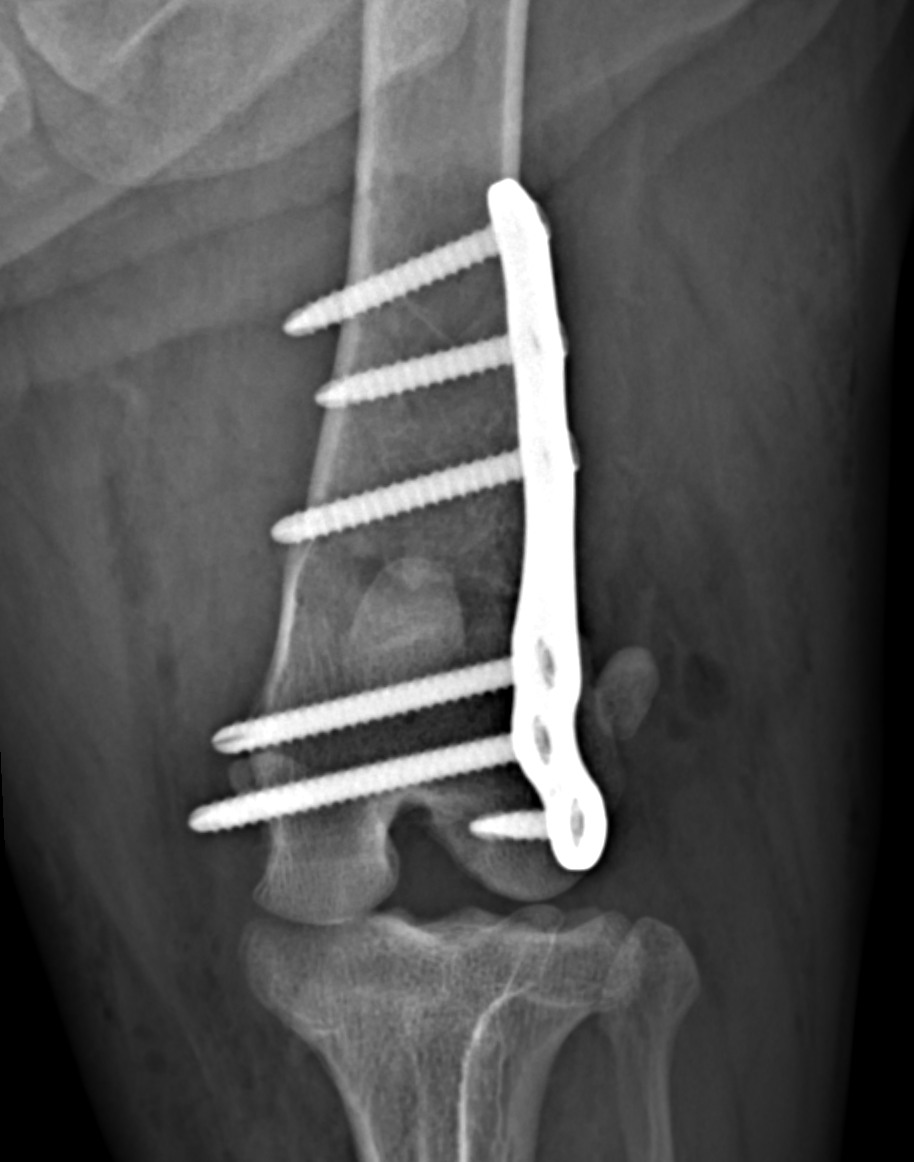

Radiografia del femore fratturato di un cane, trattata con una placca in titanio e acciaio con un'ottima riduzione e un ottimo risultato postoperatorio

Chirurgia ortopedica e traumatologica

Garantisco cure all’avanguardia per i miei pazienti a quattro zampe: utilizzo impianti di ultima generazione per ottenere risultati ottimali, ridurre il disagio post-operatorio e favorire un recupero funzionale completo. Ogni intervento è pianificato con rigore diagnostico, impiego di materiali biocompatibili e tecniche chirurgiche avanzate, tenendo sempre al centro il benessere dell’animale.